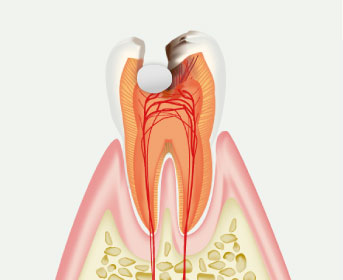

感染源を見逃さない、

取り残さない歯の神経・根の

精密な治療歯の神経や血管が入っている管=根管の治療は、従来、感覚に頼る部分が大きく困難な治療の一つでしたが、当院ではマイクロスコープなどの充実機器と経験豊富な歯科医師の知識・技術により、やりかえの少ない・感染源を取り残さない精密な治療を提供することができます。

虫歯がないのに歯が痛い、歯ぐきから膿が出る、という方はご相談ください。 -

歯の寿命を延ばすための

精密な診断・治療歯の神経を残し

長持ちさせる治療虫歯が重度まで進行すると、やがて歯の内部にある神経にまで感染が及び、激しい痛みの原因になります。

当院では、全ての神経を除去するのではなく、壊死した部位だけを見極めて取り除くことで神経をできる限り温存する部分断髄法などにも対応し、歯の健康と美しさを守るためのMTA覆髄法を行っています。 -